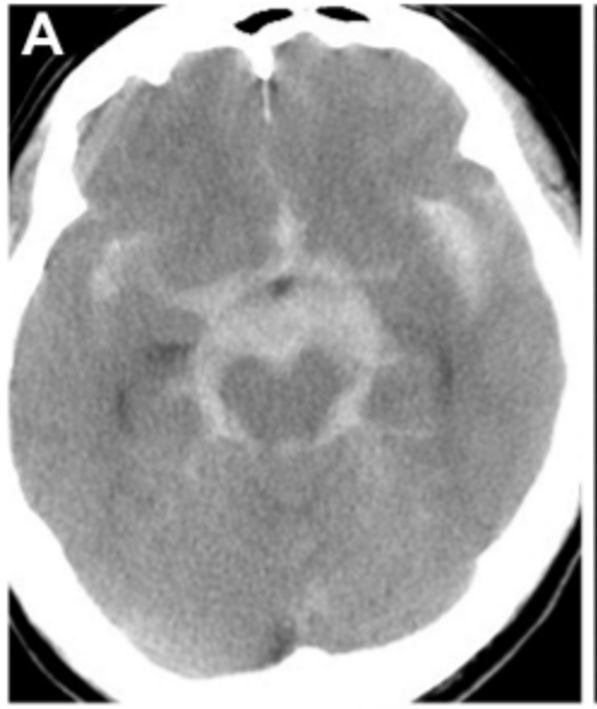

47岁男性,确诊蛛网膜下腔出血(Hunt-Hess和Kosnic 3级)(图3A)。初次就诊时,3D CTA或DSA未发现扩张或血管病变。

▼A、CT显示弥漫性蛛网膜下腔出血,是左侧脑桥前池增厚.

▼出血后18天的延迟血管造影显示左侧P1-P2段有一个不断增长的夹层动脉瘤,并具有狭窄特征(图3B)。

B,出血后18天,血管造影显示左侧P1-P2段扩张并具有狭窄征,PTA从狭窄病变的远端部分分支(箭头)。